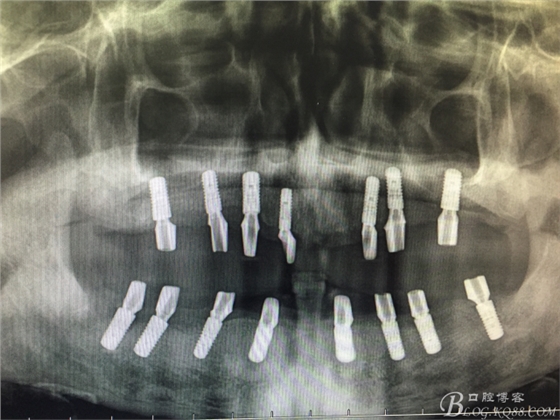

患者37歲 男 全口牙周病 手術(shù)一次完成 全程3小時全口種植修復(fù)全口種植修復(fù)全口種植修復(fù)全口種植修復(fù)全口種植修復(fù)全口種植修復(fù)全口種植修復(fù)全口種植修復(fù)全口種植修復(fù)全口種植修復(fù)全口種植修復(fù)全口種植修復(fù)全口種植修復(fù)全口種植修復(fù)全口種植修復(fù)